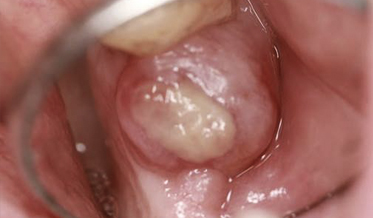

Unilateral Buccal Bifurcation Cyst: A Rare Cystic Lesion in Children and Adolescents

Sabita Rao, DMD; Vijay Parashar, BDS, MDSc, DDS; Douglas W. Beals, DDS, MS; and Olysia N. Takla, DMD